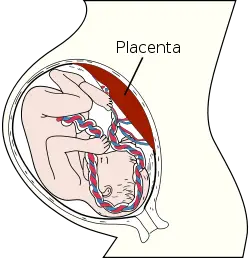

In zoology, the placenta is a temporary vascular organ that forms in the uterus of female placental mammals during pregnancy and, via an umbilical cord, connects the mother to the developing fetus. While this "true placenta" is a defining characteristic of eutherian or placental mammals, the term also is used in zoology to refer to organs with similar functions in certain nonmammalian animals, including various snakes, lizards, and sharks, up to Prototherial (egg-laying) and metatherial (marsupial) mammals. In botany, the term is used in reference to a part of a flowering plant ovary to which ovules are attached. This article will focus on the mammalian placenta.

In humans, the placenta averages 22 cm (9 inch) in length and 2–2.5 cm (0.8–1 inch) in thickness (greatest thickness at the center and become thinner peripherally). It typically weighs approximately 500 grams (1 lb). It has a dark reddish-blue or crimson color. It connects to the fetus by an umbilical cord of approximately 55–60 cm (22–24 inch) in length that contains two arteries and one vein (Yetter 1998).

As the womb grows, the placental also moves, commonly starting low in the womb in early pregnancy but eventually moving to the top of the womb. In order for the cervix to be open for delivery, the placenta should be near the top of the womb by the third trimester. When the placenta is cervix is obstructed by the placenta, it is a condition known as previa. (Vorvick and Storck 2011).